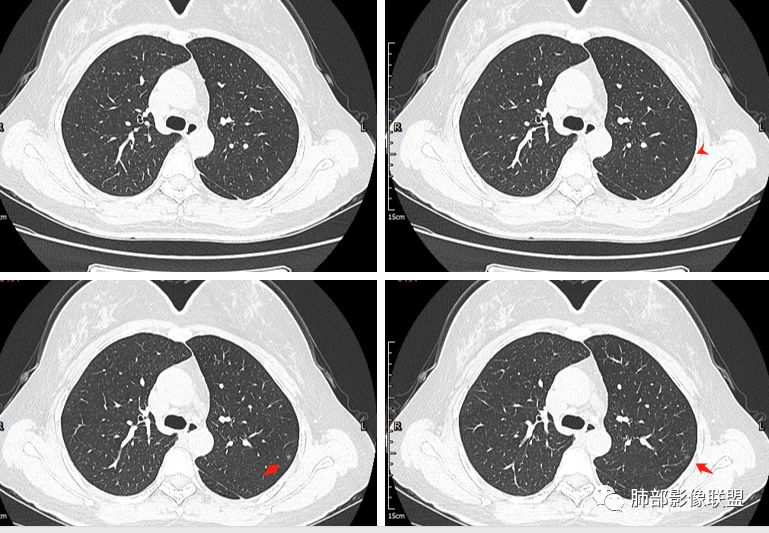

二.关于胸膜下小结节:

结节影太小,尚未能够充分反映出影像学特征。随访观察应当是恰当的处置方式。

在影像上观察到肿块或磨玻璃结节一侧的内凹,像个月牙铲形态,病理是肿瘤生长受到小叶间隔阻挡并受肿瘤内部的收缩力形成,王兆宇老师称之为“月牙铲”!对诊断肺腺癌较有特异性。